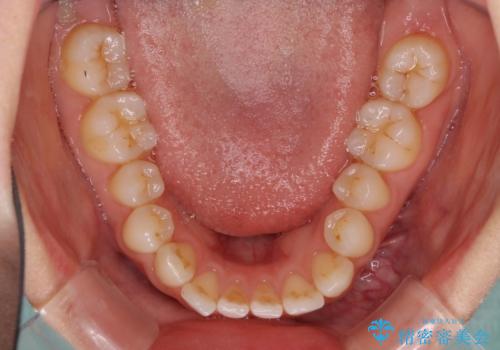

欠損による前歯のスペースが大きかったため、事前にワイヤー矯正で前歯の位置を大きく動かし、その後は上下をインビザラインで整えることとしました。

前歯のスペースは、堅い線維の通った歯肉があり、幅も大きかったことから、歯肉切除を行った上でワイヤー矯正により移動を行いました。また、上唇小帯も歯間部付近まで付着していたため、合わせて切除しました。

ワイヤー矯正により、インビザラインよりも早く、歯軸の向きもコントロールしながら移動させることができました。